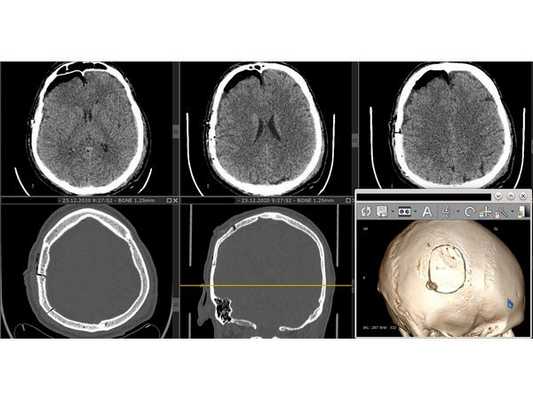

КТ головного мозга в первые сутки: выявлен линейный перелом лобной кости, переходящий на основание передней черепной ямки, и очаги ушиба полюсных отделов правой височной и лобной долей головного мозга (II вид по Корниенко), травматическое субарахноидальное кровоизлияние. Также выявлен двусторонний перелом нижней челюсти. КТ головного мозга на вторые сутки: выявлена трансформация очага ушиба правой лобной доли во внутримозговую гематому (агрессивный очаг ушиба головного мозга).

КТ головного мозга на вторые сутки: отсроченное формирование внутримозговой гематомы в правой лобной доле

В связи с отрицательной динамикой неврологического статуса и рентгенологической картины принято решение об оперативном вмешательстве: 1. Удаление внутримозговой гематомы через фрезевое отверстие; 2. Нижняя трахеостомия (для проведения длительной искусственной вентиляции лёшких). Техническая сложность заключалась в широких лобных пазухах пациента, т. к. фрезевое отверстие весьма желательно было наложить, не вскрывая лобную пазуху, но в то же время непосредственно в проекции внутримозговой гематомы. Для этого выполнена предоперационная разметка проекции внутримозговой гематомы на свод черепа. Операция №1 (длительность — 25 минут): ⠀• выполнен 4 см линейный разрез мягких тканей в лобной области справа параллельно естественным морщинам; ⠀• скелетирована кость, произведён гемостаз электрокоагуляцией по ходу доступа, визуализирован линейный перелом лобной кости; ⠀• с помощью краниотома наложено фрезевое отверстие и гемостаз воском; ⠀• твёрдая мозговая оболочка вскрыта крестообразо, визуализирован выход внутримозговой гематомы на кору головного мозга; ⠀• путём аспирации и отмывания физиологическим раствором удалена внутримозговая гематома общим объёмом около 30 мл; ⠀• произведён гемостаз перекисью водорода, дефект твёрдой мозговой оболочки укрыт материалом Surgicell, костная стружка уложена во фрезевое отверстие; Операция №2 (длительность — 15 минут): ⠀• выполнен 3 см линейный вертикальный разрез мягких тканей в проекции трахеи; ⠀• тупым и острым путём обнажена передняя поверхность трахеи и взята на крючок; ⠀• П-образно рассечены два полукольца и заведена трахеостомическая трубка №8.5; ⠀• наложены швы на мягкие ткани, трахеостомическая трубка подшита к коже, наложена асептическая повязка. Всё оперативное вмешательство вместе с анестезиологическим пособием уложилось в 1 час, выполнено с минимальной кровопотерей.

После операции состояние пациента постепенного восстановилось до ясного. На третьи сутки после операции проведена контрольная КТ головного мозга. Также пациент был оперирован по поводу скелетной травмы, деканулирован на восьмые сутки после операции. Операционная рана и трахеостома зажили.

Представленный пример может быть рассмотрен как вариант хирургической тактики при агрессивных очагах ушиба головного мозга. Так, при минимальной хирургической агрессии решены основные проблемы: за один наркоз удалена внутримозговая гематома и выполнена трахеостомия, позволившая освободить полость рта для дальнейшей работы челюстно-лицевого хирурга и проведения продлённой искусственной вентиляции лёгких. Предоперационная 3D-разметка позволила рассчитать доступ — непосредственно в проекции внутримозговой гематомы, но без вскрытия лобной пазухи. Стоит отметить, что удаление травматической внутримозговой гематомы через фрезевое отверстие технически вполне выполнимо, хотя, конечно, обзор весьма ограничен.